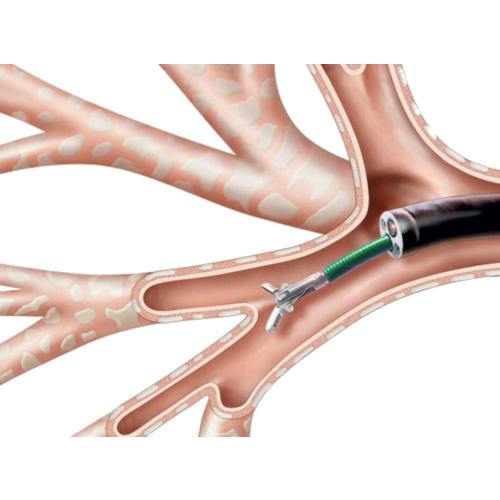

Фотографии и информация о бронхоскопии при туберкулезе